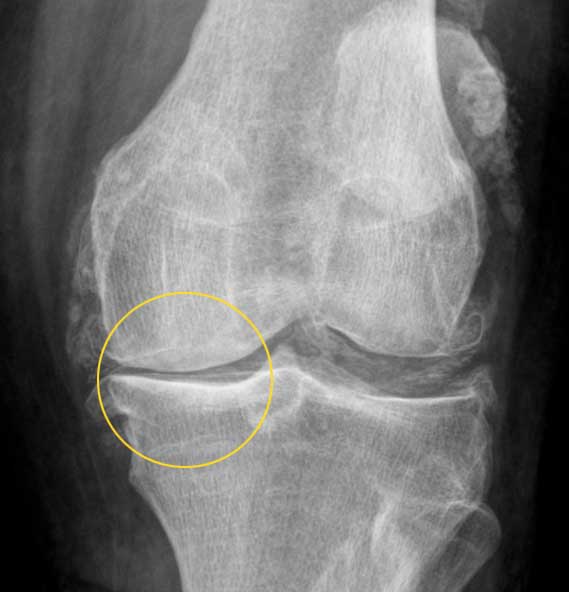

Bildgebende Verfahren: Röntgen, Ultraschall und MRT

Der wichtigste Schritt zur Darstellung von Knorpelschäden bei Gonarthrose ist eine Röntgenaufnahme des Knies. Es zeigt deutlich Veränderungen des Gelenkspalts. Wo Knorpel im Knie abgebaut wurde, nimmt der Abstand der Knochen im Röntgenbild ab. Für ein eindeutiges Ergebnis ist es wichtig, dass das Röntgenbild im Stehen unter Gewichtsbelastung angefertigt wird. Ohne Belastung ist eine Verschmälerung des Gelenkspalts oft nicht sichtbar. Röntgen ist der Goldstandard der Diagnostik einer Gonarthrose.

Folgende radiologische Arthrosezeichen geben einen eindeutigen Hinweis auf Kniearthrose:

- Der Gelenkspalt im Knie ist verengt.

- Es kommt zur Sklerosierung (Verdichtung) des Knochens unter dem Knorpel aufgrund der erhöhten Belastung im Kniegelenk. Man sieht eine Aufhellung im Knochen.

- Es bilden sich Knochensporne (Osteophyten).

- Manchmal ist eine Chondrokalzinose (Ablagerung von Kalzium in Knorpel) sichtbar, die aber keinen krankheitsauslösenden Effekt haben muss.

Für die Röntgendiagnostik der Kniearthrose sehr wichtig ist die seitenvergleichende Aufnahme beider Kniegelenke unter Belastung. Der Patient beugt seine Kniegelenke dabei um 20 Grad.